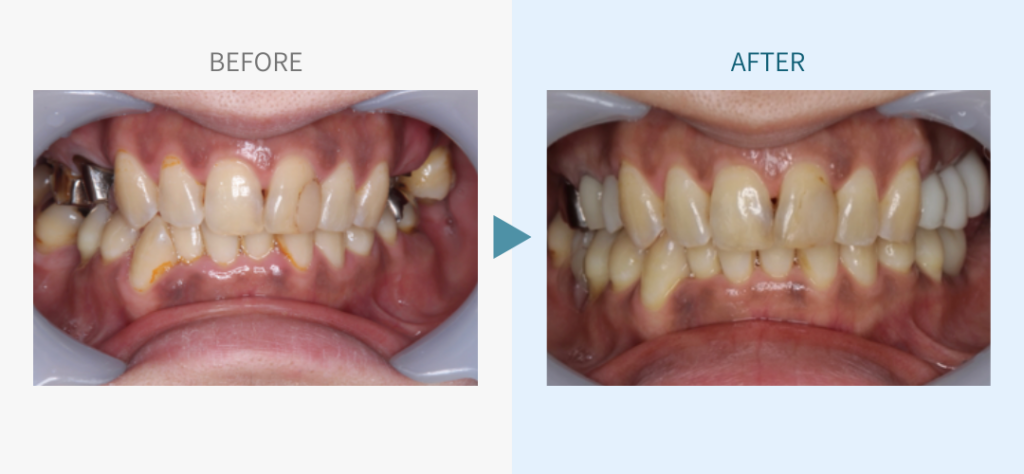

デンタルチームジャパンでは、サイナスリフト(上顎洞底挙上術)や骨造成など、他院で「骨が足りない」と断られた難症例にも対応しています。

こちらではその一部の症例についてご紹介します。

※本ページは当院で行った一症例のご紹介です。治療結果や経過には個人差があり、同様の結果をお約束するものではありません。すべて自由診療です(保険適用外)。